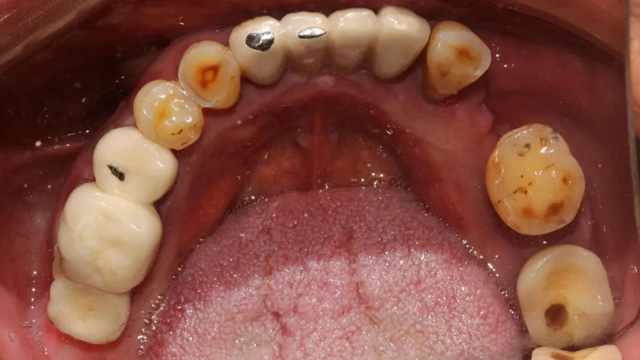

上半口即刻种植后全景片

两周后吴叔叔回院拆线,完成了下牙的多颗种植治疗。别看下面的种植数量少,难度却并不低。据余国庆医生介绍,有一颗种植体采用的是倾斜植入,因为之前的种植体周围有感染,拆除种植体后只能在旁边一个极其有限的范围内种植,种植窝洞的位置需要非常精准,很考验医生的技术和经验。

下颌即刻种植后全景片